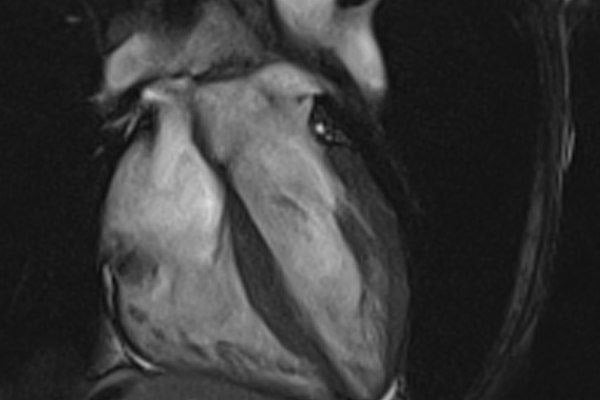

- MRIOnline Mastery Series: Cardiac MRI of Non-Ischemic Cardiomyopathy 2021 (CME VIDEOS) In this series Dr. Stefan Zimmerman discusses cardiac MRI of non-ischemic cardiomyopathy. Non-ischemic cardiomyopathy is a common cause of heart failure and MRI can be a vital tool in narrowing down the diagnosis. Dr. Zimmerman reviews the reasons these patients present to MRI, the most commonly encountered diagnoses in the non-ischemic category and the best approach for identifying disease.

- Cardiac Search Pattern in the Setting of Dilated Cardiomyopathy

- Dilated Cardiomyopathy